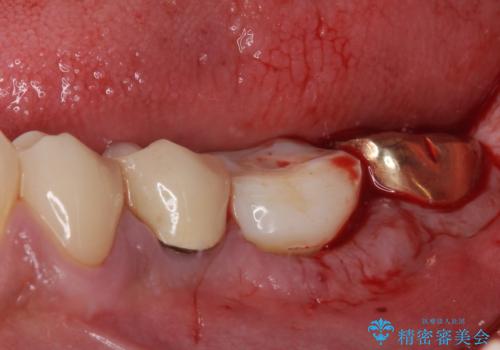

そのため、当院に新しく導入した手法により、抜歯をした日にインプラントを埋入し、そのままを仮歯を装着することで、他の歯への負担を軽減する計画を立てました。

インプラント埋入時に植立具合の安定性を測定したところ、十分な数値が得られたため、速やかに仮歯を装着して咬合回復をさせることができました。

抜歯を含めた外科処置を1回に抑えることができ、あっという間に治療を終えることができました。